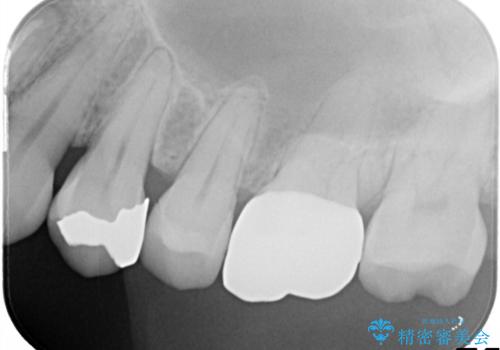

- 「何もしなくても歯が痛む、咬むと歯が痛む」を主訴に来院された患者さんです。検査の結果、歯髄の部分壊死と診断しました。根管治療を行いファイバーコアとオールセラミッククラウンで治療を行いました。

神経が死んでしまった原因はプラスチック(保険適用治療)の被せ物が劣化し歯と被せ物の間に生じた隙間からのリークが原因だと考えます。